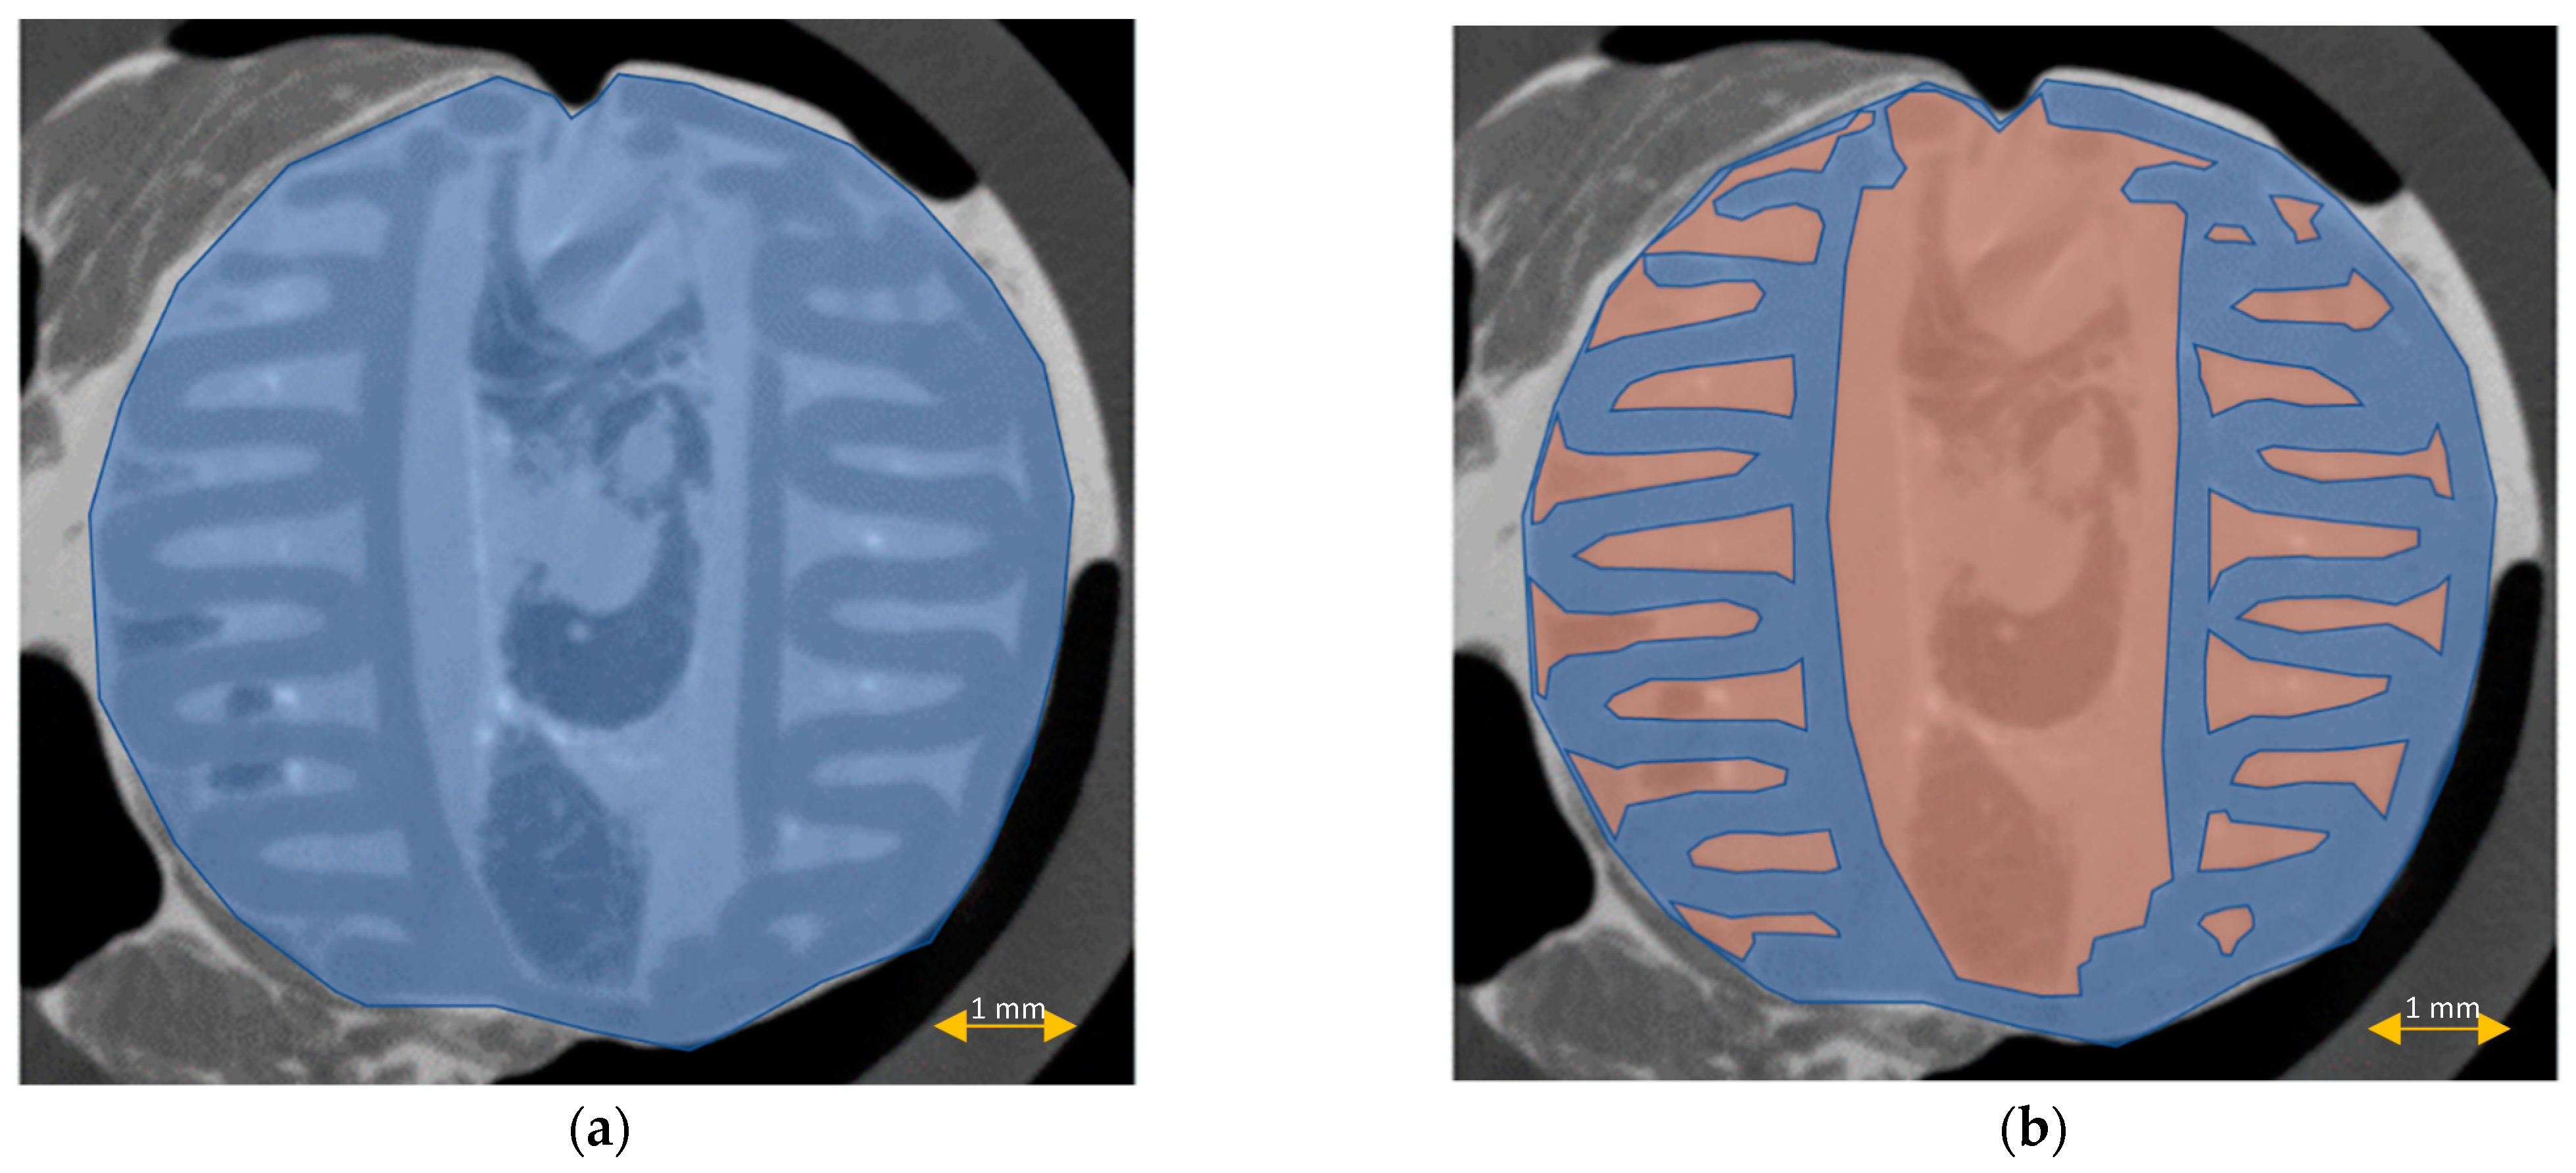

3.5. Scaffold μCT Imaging

3.6. Scaffold Cross-Sectional Analysis